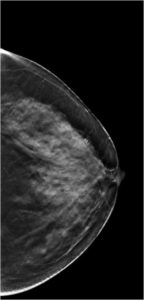

59 Yr old female, referred from outside for suspicious microcalcifications in left breast.